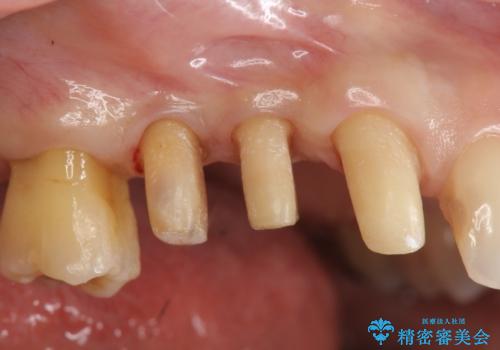

部分矯正を含む 歯周病治療 (再生治療・歯周ポケット除去・MTM・連結補綴)

検査の結果、強い歯ぎしりによる歯の周囲の骨の吸収が認められたため歯槽骨の再生・歯周ポケットの除去・力に対抗する連結補綴・補綴前処置としての小矯正を計画します。

今回連結補綴を行うにあたり、歯周病の問題を解決するために再生療法・歯周ポケット除去手術を、またより歯の神経を保存し力に対抗できる環境を整えるために小矯正を行い精度の高いメタルボンドクラウンを製作することができました。